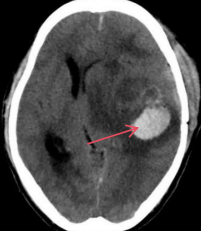

注:图 3 4 均为头颅 CT 平扫检查结果图片,图 3 为脑出血患者头颅 CT 扫描显像,红色箭头处表示该处有高密度出血, 周围脑组织水肿,中线结构向右侧移位;图 2 为正常颅脑 CT 扫描显像,双侧脑组织对称,灰白质对比清楚,中线结构居中。